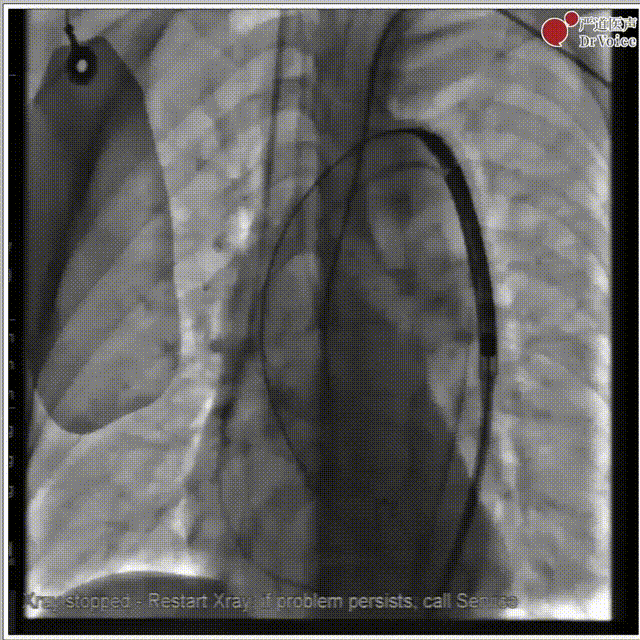

4. 植入23mm Evolut PRO瓣膜,过弓及瓣膜定位。

过弓,植入瓣膜

主动脉根部造影